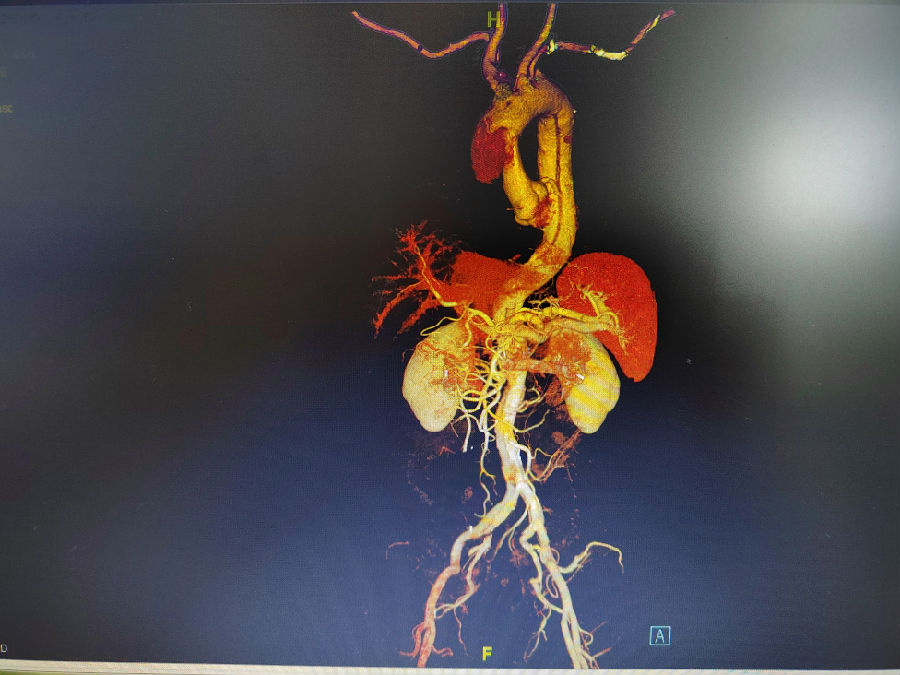

病人至急诊就诊,一旦急诊心脏超声、主动脉CT提示主动脉夹层,并存在血性心包积液,那么,该患者的术前准备紧凑性及进入手术室手术的画面,可能会是“x2.0”甚至更高倍数的播放速度。

术后复查CT